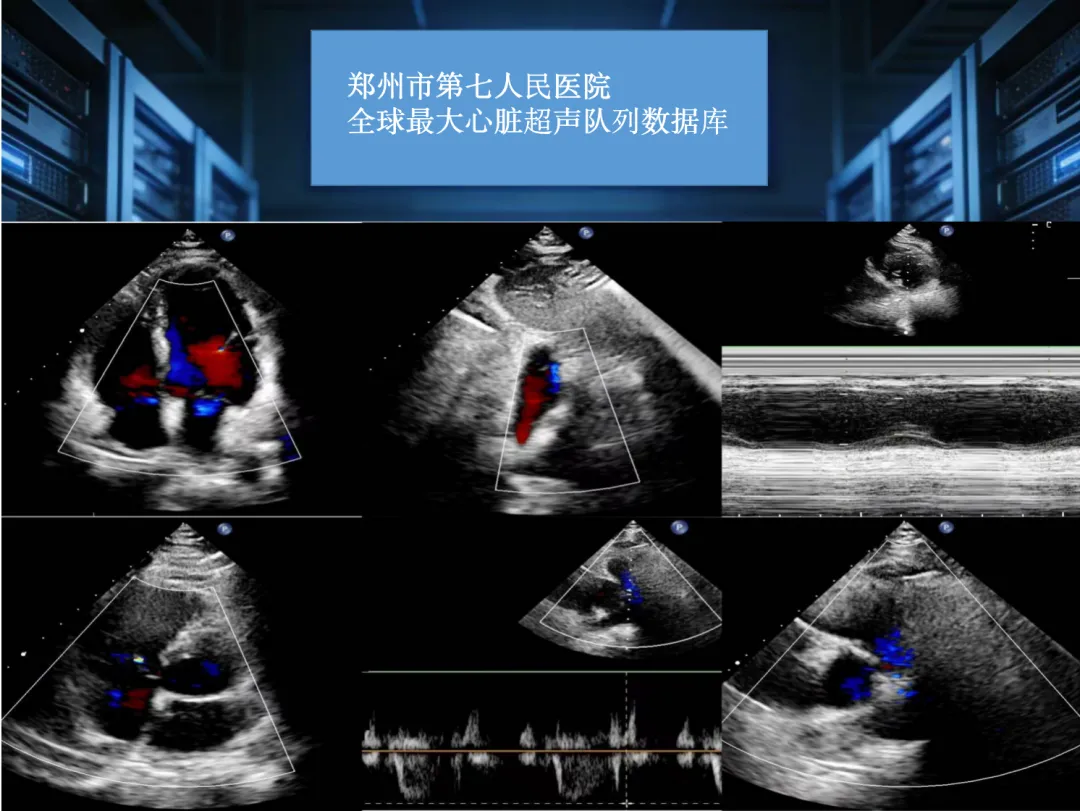

而现在,郑州市第七人民医院联合顶尖专家团队,搞出了一个“超级大脑”——全球最大队列心脏超声报告生成大模型!它可不是凭空冒出来的,而是基于15万例真实患者的临床数据,经过了全国六大权威医疗中心的验证,专门用来帮医生快速、准确地生成心脏超声报告。

先说说心脏超声,这玩意儿是医生看心脏结构和血流情况的首选手段,就像给心脏做一次“高清体检”。但传统的体检报告,全靠医生一双眼睛盯着屏幕看,一边测量一边手动写报告,费时费力不说,还容易因为经验不同,导致报告质量参差不齐。